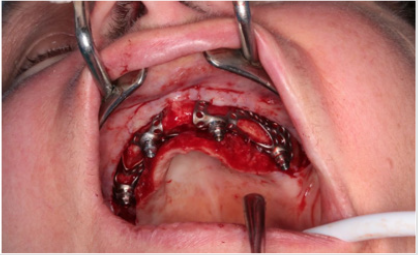

Distant forces were used as they would normally act on the implant from the dental crown. We used data obtained from scientific literature according to which magnitude occlusal forces can be between 100 and 800 N. In the first analysis, maximum 800 N occlusal force was defined. Its result is presented in Figure 7 It is notable that stresses only raised at the acting point of the force. Stress intensity was 287.28 MPa for maximum occlusal load. Another scenario was also investigated in which the frontal part of the implant was loaded with the lowest, while the back of the implant was loaded with the highest occlusal forces. Figure 8 presents the results of this loading scenario with the maximum stress level of 207.6 MPa. It is notable in this case that highest stresses raised at the back of the implant at the acting points of the forces. Different force variations were all analysed from minimum to maximum loads. Figure 9 shows the set of completely linear results. Highest stress intensity was 287.28 MPa for maximum occlusal forces. The studied implant was inserted after manufacturing. Implant fitting to the bone ridge of the patient can be seen in Figure 10.